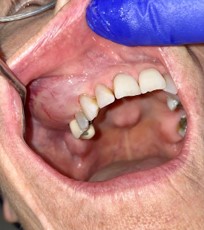

A 68-year-old female presented to her dentist for evaluation of an asymptomatic “big bulge” of her right maxilla (Figure 1). She first noticed it 5 months earlier and claimed that it had continuously enlarged since that time. At examination there was a large, sessile, smooth-surfaced mass which was firm to palpation. The expansion extended from the right lateral incisor area to the long-edentulous molar region and was virtually all toward the facial, with minimal elevation of the crestal region of the alveolus. The surface mucosa was unremarkable and there were no other masses present, except for a small, lobulated torus palatinus. No neckmass could be detected.

Figure 1: Clinical appearance of lesion: large, firm, smoothsurfaced mass of right maxilla.